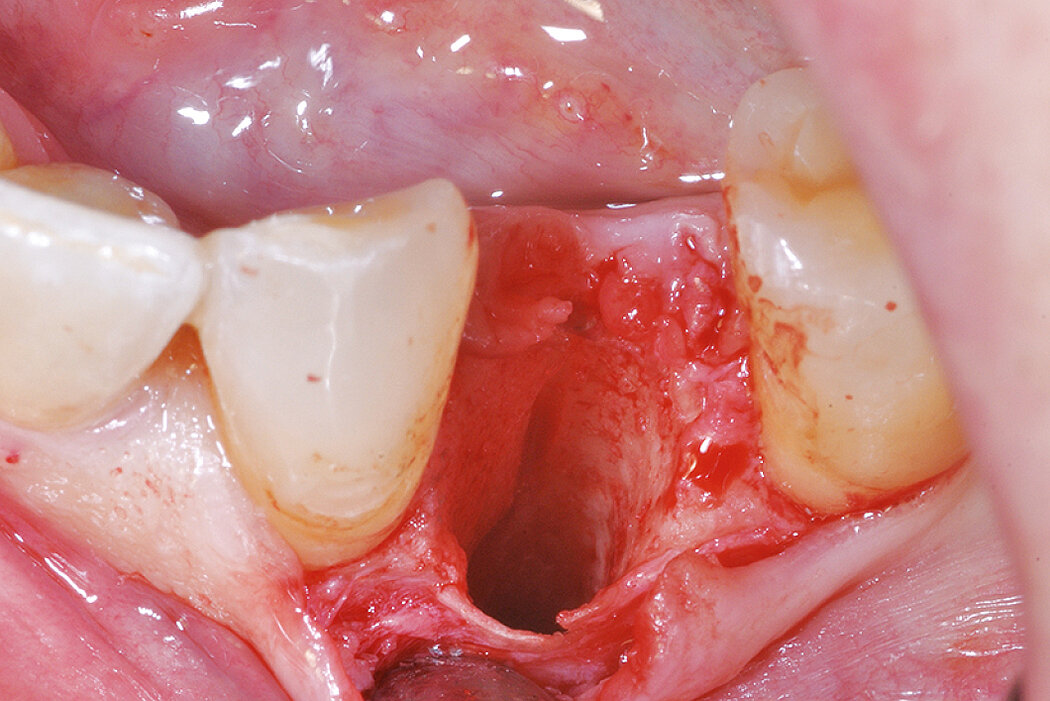

Ridge Preservation for preserving the red white esthetics for late implant placement (open-healing approach)

Clinical challenge

Preservation of red-white esthetics by alveolar Ridge Preservation measures for a late implantation.

Aim / Approach

Augment the bone tissue and preserve the soft tissue for implantation at a later point in time. The goal is to attain an appealing esthetic result for the mid-term temporary reconstruction.